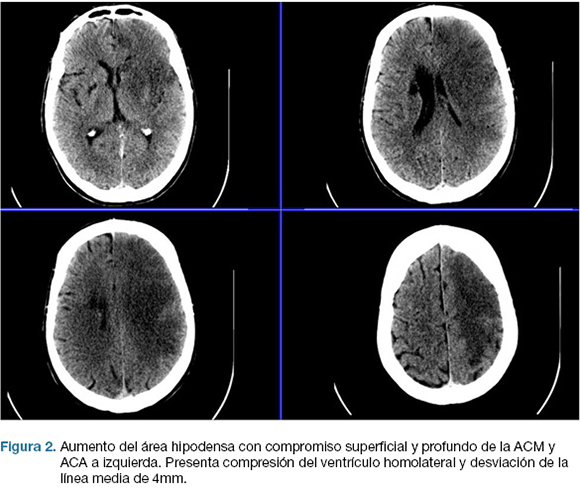

Se realizo TC de cráneo, que confirma área de isquemia en territorio de la arteria cerebral media (ACM) y arteria cerebral anterior (ACA) izquierda. (Figura 1). No se realizó fibrinolíticos intravenosos por encontrarse fuera de los plazos de tiempo. A las 17 horas de la evolución deprime conciencia, constatándose apertura ocular al llamado, no cumple órdenes, mutismo afásico, CGS: 9. Se reitera TC de cráneo que evidenció un aumento extenso del área de infarto de la ACM, y ACA, con efecto de masa dado severo. (Figura 2)